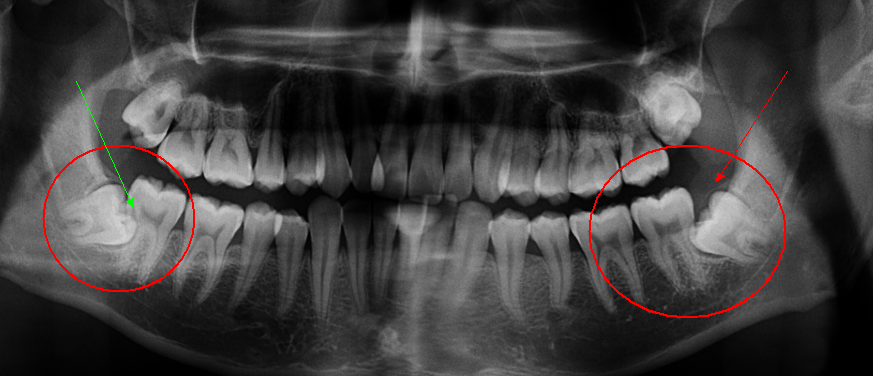

一般来说,以下7种类型的智齿要尽快拔掉(具体见下图):

1.垂直阻生型智齿

2.远中阻生型智齿

3.近中阻生型智齿

4.水平阻生型智齿

5.颊向阻生型智齿

6.舌向阻生型智齿

7.倒置阻生型智齿